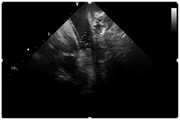

图4是示例J型导丝头端(软头)位于上腔静脉内呈现明显高密度影;Figure 4 is an example of the J-shaped guide wire tip (soft tip) located in the superior vena cava showing obvious high-density shadow;

①穿刺股静脉后将J型导丝头端(J型软头)送入上腔静脉,超声扇面中可见J型导丝头端,呈高密度影。(见图4)①After puncturing the femoral vein, the tip of the J-shaped guide wire (J-shaped soft tip) was sent into the superior vena cava. The tip of the J-shaped guide wire was seen in the ultrasound fan, showing a high-density shadow. (see Figure 4)